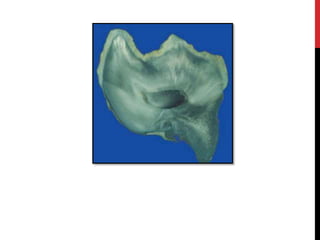

GROSS SPECIMEN

• #46 Fig. 4.2a–d Amelogenesis imperfecta of the hypomineralised type. The enamel cap is worn away due to masticatory forces leaving a bare dentin surface with enamel remnants present only at the cervical part of the crown (a). Gross appearance (b), cut surface (c) and ground section (d) showing thin and friable enamel cap